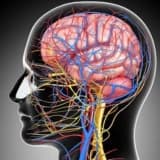

Migren baş ağrılarının dəqiq səbəbi məlum deyil. Tədqiqatçılar; Onlar beyində serotonin və endorfin səviyyələrindəki dəyişikliyin roluna mümkün qədər inanırlar. Seratonin (nörotransmitter) trigeminal sinir yolları ilə ötürülən ağrıları tənzimləyən beyin kimyəvi maddəsidir. Trigeminal sinirlər üz, göz, burun, sinuslar, qan damarları və beyin qabıqlarından yaranan ağrının əsas yollarıdır. Endorfinlər beyin və spin hord tərəfindən istehsal olunan təbii ağrı kəsici kimyəvi maddələrdir. Tetikler Çox vaxt miqren baş ağrılarının dəqiq bir səbəbi yoxdur, lakin yorğunluq, qidalar, ətraf mühit faktorları, yüngül baş travması, hormonal amillər və dərmanlar ağrıya səbəb ola bilər.